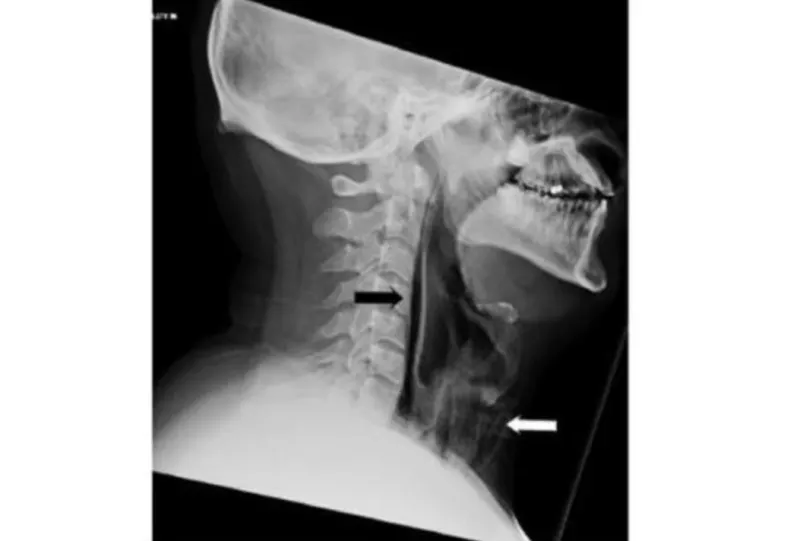

Los escaneos confirmaron el problema. Las pruebas mostraron vetas de aire reales en la región retrofaríngea y enfisema quirúrgico extenso en el cuello anterior a la tráquea. En otras palabras, al tratar de retener su estornudo, en realidad se hizo un pequeño agujero en la garganta.